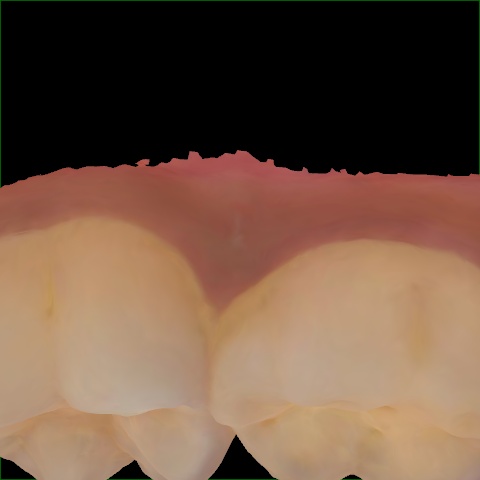

Incorrect Quality Level

The reference annotation for this image is

None

.

Please select the correct quality level.

Image 345 / 1715

Annotated as "Good"